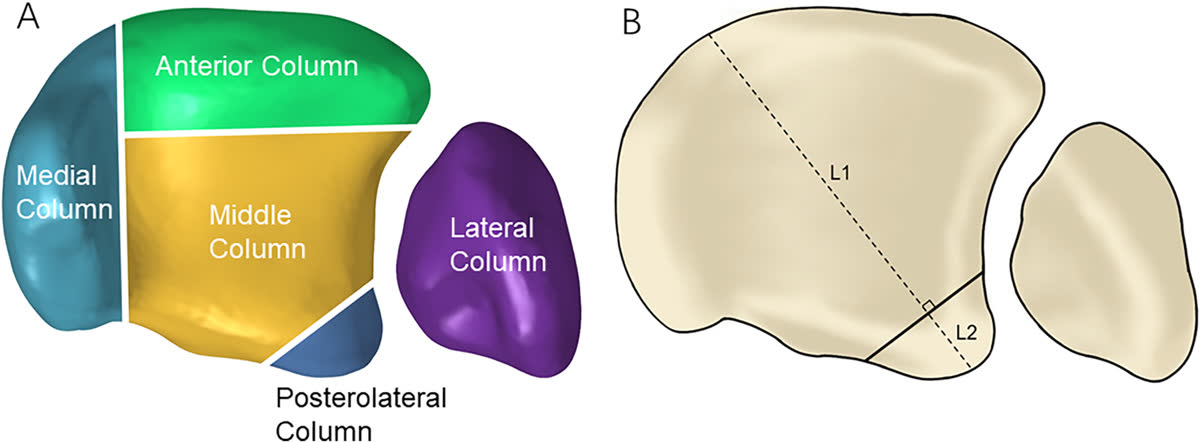

Пятиколонная классификация (Liu, 2025)

Наиболее современная классификация, основанная на 3D-картировании переломов и конечно-элементном анализе распределения нагрузки (244 перелома пилона, 2018–2024). Выделяет 5 колонн:

- Медиальная колонна — перелом медиальной лодыжки

- Передняя колонна — передняя 1/3 суставной поверхности дистального отдела большеберцовой кости (за исключением медиальной лодыжки)

- Средняя (центральная) колонна — задние 2/3 суставной поверхности, исключая медиальную колонну и заднюю лодыжку. Отражает импакцию центральной зоны плафона — ключевой компонент, не выделявшийся в предшествующих классификациях

- Заднелатеральная колонна — задняя лодыжка (фрагмент Volkmann)

- Латеральная колонна — дистальный отдел малоберцовой кости + повреждение дистального межберцового синдесмоза, рассматриваемые как единая функциональная единица

Линия перелома на суставной поверхности имеет характерное V-образное распределение с ветвями, расходящимися от зоны медиальной лодыжки и вырезки малоберцовой кости. Наиболее частый паттерн — трёхколонные переломы, затем двухколонные.

Межнаблюдательская надёжность: каппа = 0,653 (P<0,001); внутринаблюдательская: каппа = 0,708 (P<0,001) — сопоставима с AO/OTA и превосходит ранние колонные классификации [Liu et al., Orthop Surg, 2025; PMID: 39579007].

Пятиколонная теория — это продолжение теории колонн, которая преобразовалась тем, что задняя колонна была переосмыслена на среднюю (или привычнее для нас, центральную) и добавлена постеролатеральная колонна (фрагмент Фолькмана). Клинических и практических данных по данной классификации пока недостаточно, чтобы однозначно делать какие-то выводы о таком подходе.